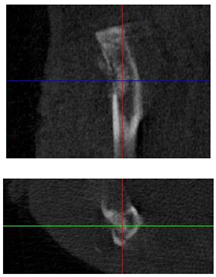

| Figurative Point | |||

|---|---|---|---|

| 3 | 5 | 8 | |

| 3D model and orthogonal projections Initial | ![]() | ![]() | ![]() |

![]() | ![]() | ![]() | |

| 3D model and orthogonal projectionsAfter implantation period of 3 months | ![]() | ![]() | ![]() |